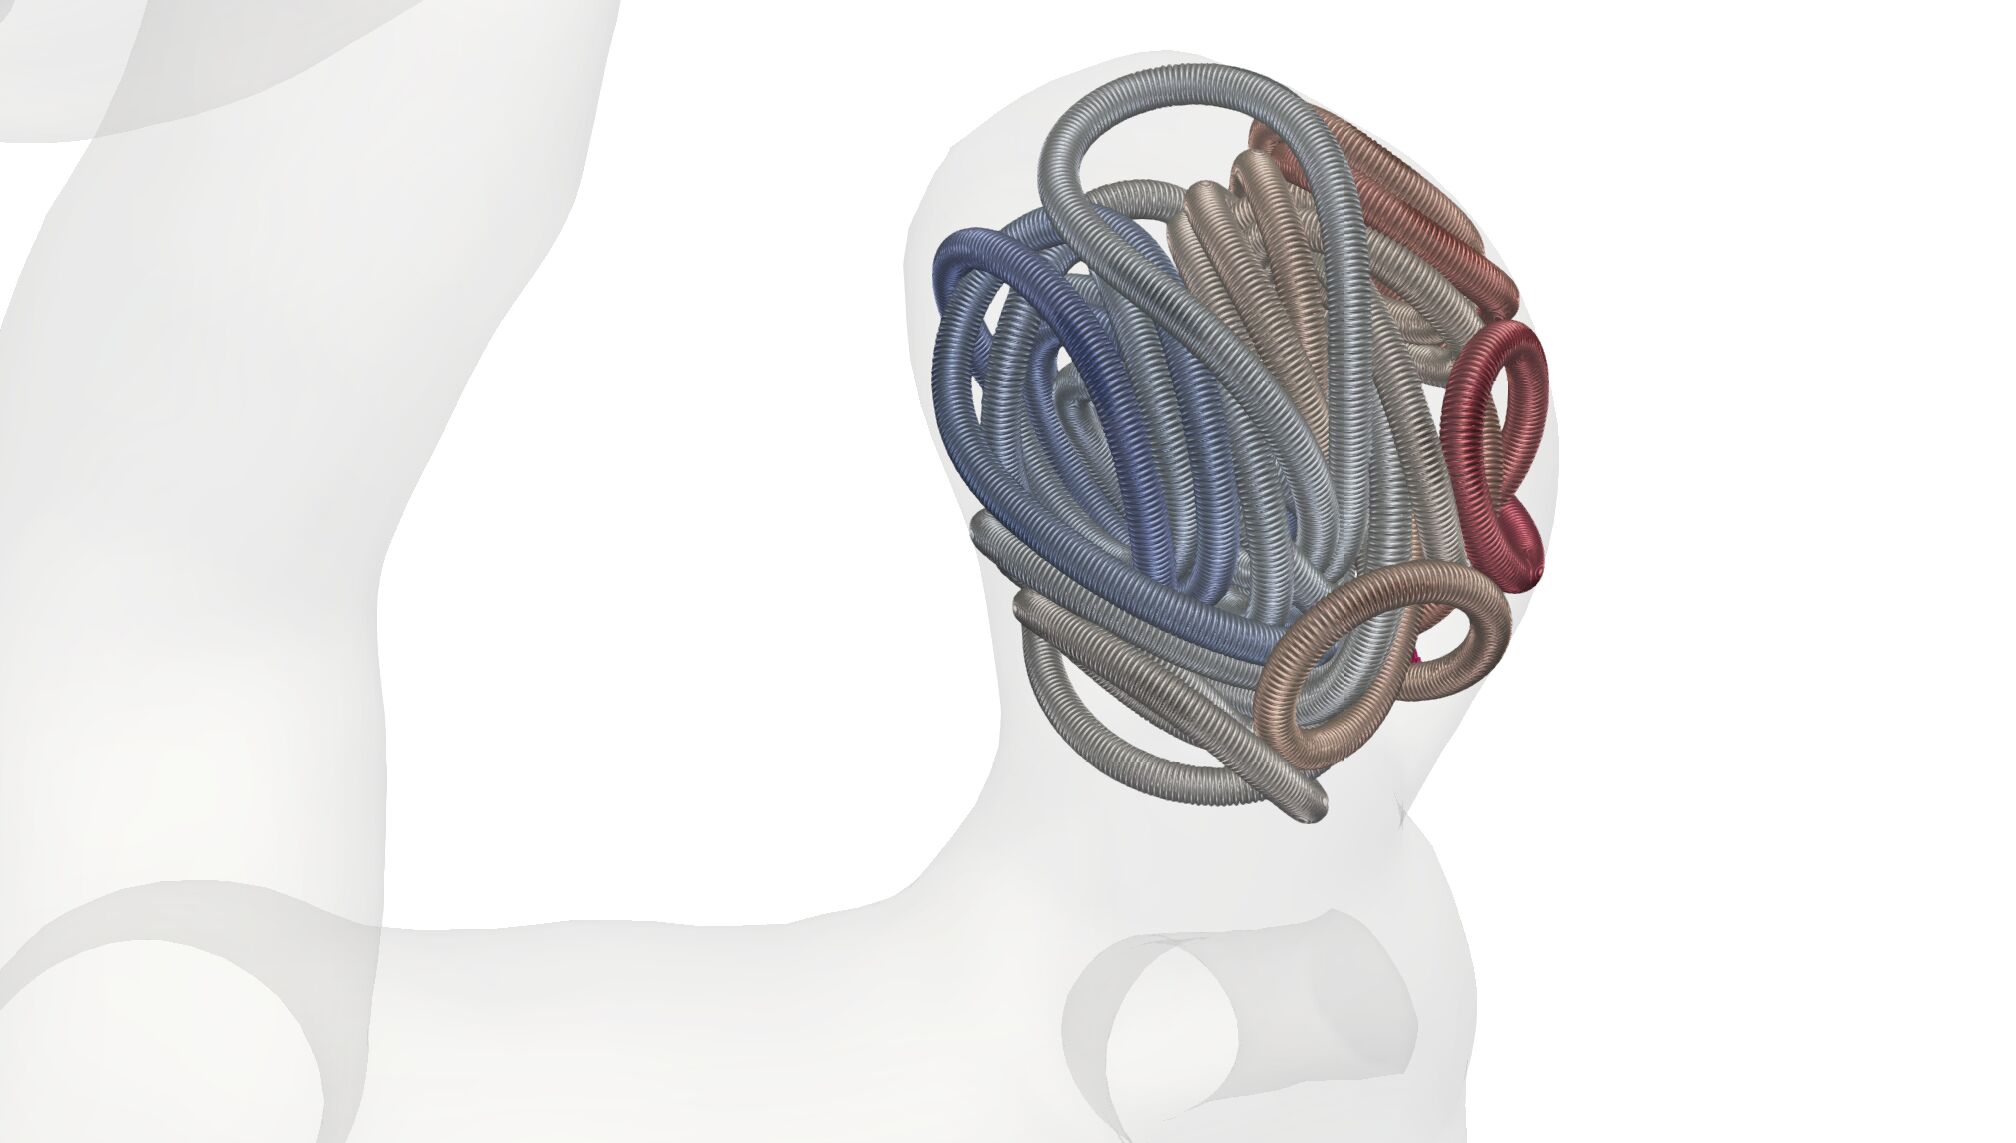

In this section, we study virtual coil placements by means of our numerical method. We begin by simulating the embolization of coils with different shapes into the small aneurysm (see Fig. 2 (top)). We use shapes that are a straight, a helix pre-shaped one and a 3D coil motivated by [51]; see Fig. 12. The point of insertion can be seen on the right of each picture at the tip of the micro-catheter.

The coils are chosen such that a global packing density is reached in the aneurysm (see red zone in Fig. 2). We observe that a straight coil leads to a placement where the coil is protruding into the artery. For the helix and 3D coil, this is not the case. Their diameter is set to which is smaller than the aneurysms diameter (compare to Fig. 2) leading to a more uniformly distributed placement. In terms of their cross-section distribution, we can see that the distribution of the coil at the neck is the highest for the 3D coil whereas for the straight and helix coil there are still openings at the neck.